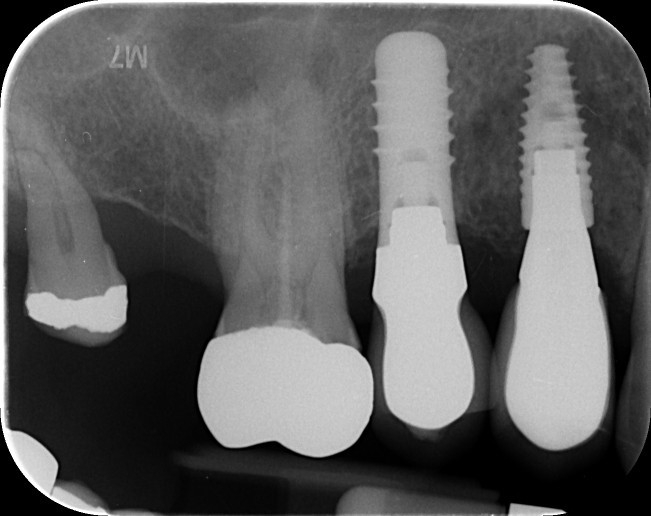

Intentional replantation can be a predictable and viable treatment option. In this case a long LR7 not suitable for root end surgery. No cracks visible under the microscope, MTA root end filling. First radiographic review in 1 month.🙃